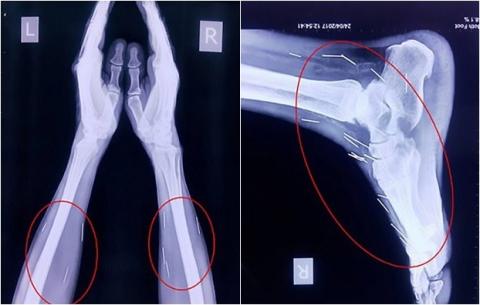

Kết quả chụp X-quang cho thấy có đến 75 cây kim trong cơ thể của

ông Badrilal Meena.

Kết quả chụp X-quang ghi nhận, bên trong bàn chân của ông Meena có nhiều cây kim sắc nhọn. Không những vậy, bác sĩ còn phát hiện ra rất nhiều kim ở cánh tay và cổ của bệnh nhân, tổng cộng có đến 75 cây.

Có 40 cây nằm trong cổ họng, 25 cây ở chân phải, số còn lại nằm ở hai

cánh tay.

Trong số 75 cây kim tìm thấy trong cơ thể ông Meena, có 40 cây nằm trong cổ họng, 25 cây ở chân phải, số còn lại nằm ở hai cánh tay.